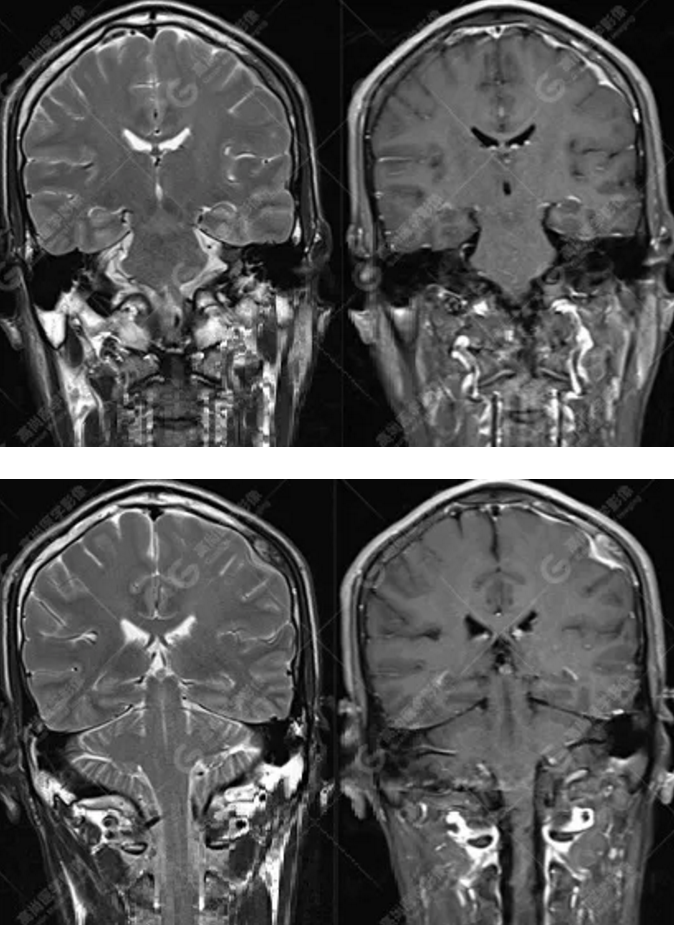

中年男性,反復(fù)出現(xiàn)手腳抽搐、暈倒伴意識(shí)喪失3年余,臨床擬診癲癇發(fā)作,后到高尚醫(yī)學(xué)影像診斷中心行MR檢查。

MR圖像

MR診斷

左側(cè)額頂部顱骨骨質(zhì)破壞并相鄰硬腦膜增厚強(qiáng)化,考慮Rosai Dorfman病(RDD)可能,需與朗格漢斯細(xì)胞組織細(xì)胞增生癥鑒別。